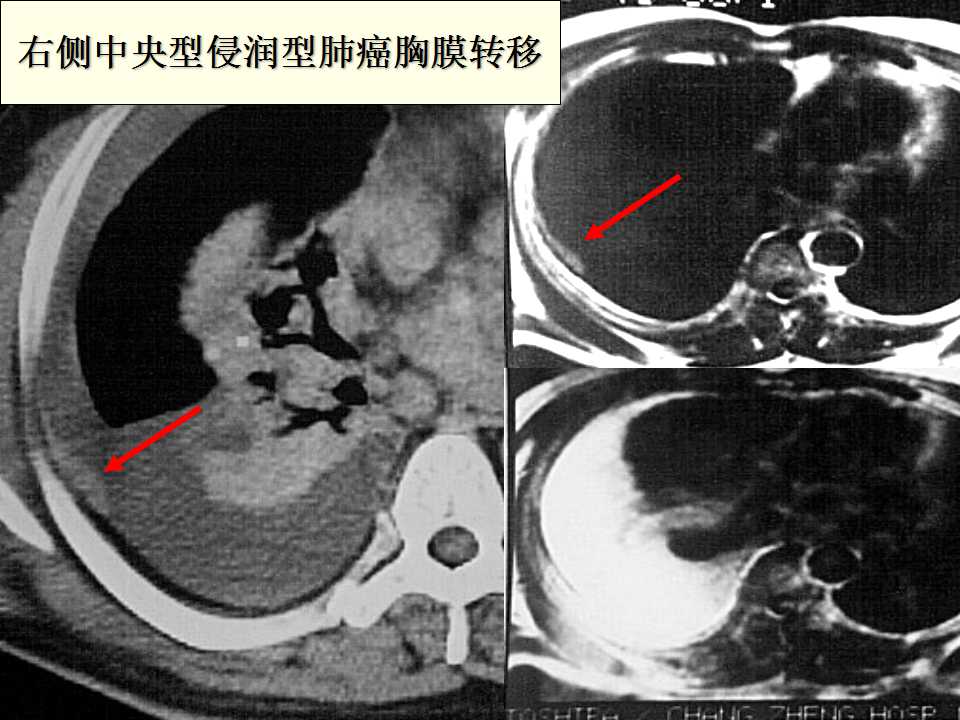

肺癌影像诊断